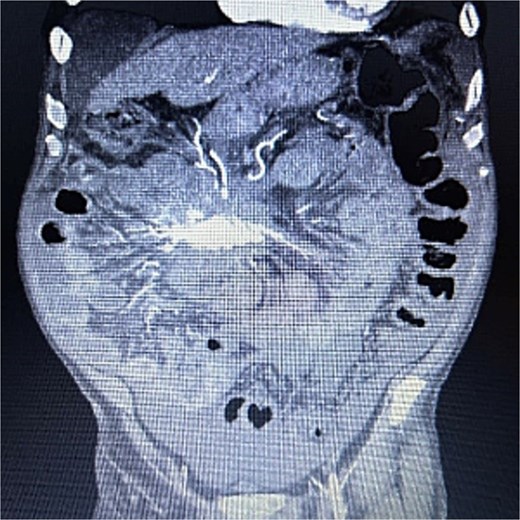

A 83-year-old male presented to his primary care physician with a 6-week history of vague postprandial abdominal pain with associated diarrhea and a 5-lb weight loss. CT abdomen/pelvis showed a 7 × 5 cm spiculated mass at the root of the mesentery involving the superior mesenteric vein and multiple mesenteric arterial branches, and associated small bowel edema and thickening (Fig. 1). He was referred to a surgical oncologist. Tumors markers including CEA, CA 19–9, Chromogranin A, serum serotonin, and urinary 5-HIAA were unremarkable. Octreotide scan showed mild central uptake at the location of the mesenteric mass (Fig. 2). Diagnostic laparoscopy showed mesenteric mass at the root of the mesentery and biopsy revealed fibrous tissue with calcifications and no evidence of malignancy. He was referred to a medical oncologist and began Lanreotide injections for presumed neuroendocrine tumor. He completed 12-months of Lanreotide therapy, however he remained symptomatic with abdominal pain, diarrhea, and ongoing weight loss. He was referred to a tertiary cancer center, but no treatment was offered in the absence of proven malignancy. He then saw another surgeon who obtained a Ga-DOTATATE PET CT scan which showed moderate ascites, an increase in size of the mesenteric mass to 7.3 × 6.3 cm, low level of tracer at the periphery of the mass, and intense activity within the 2nd and 3rd portions of the duodenum. He was referred to an advanced endoscopist for EGD/EUS, which did not show a duodenal mass. Due to ongoing symptoms he was scheduled for repeat diagnostic laparoscopy with possible resection of mesenteric mass versus repeat biopsy. On the morning of surgery, he presented with dizziness and acutely worsening abdominal pain. He was tachycardic and hypotensive with abdominal distention and peritonitis on exam. Due to concern for a perforated viscus the decision was made to proceed with exploratory laparotomy. He was found to have purulent ascites and dusky small bowel with edema and central swirling atop a large, calcified mesenteric mass. Upon further inspection, a single site of small bowel perforation was identified and there was leakage of succus into the abdominal cavity. A palliative resection of the perforated small bowel and adjacent mesenteric mass was performed. 100 cm of small bowel was resected en bloc with the mesenteric mass, but residual gross tumor was left at the base of the superior mesenteric artery and encasing the middle colic artery (Fig. 3). Intra-operative doppler and Firefly were used to determine perfusion of the remaining 120 cm of small bowel and a side-to-side small bowel anastomosis was performed. He was hemodynamically stable at the termination of the procedure, extubated, and admitted to the intensive care unit for close observation. Post-operatively, he converted into atrial fibrillation with rapid ventricular response and ultimately died from cardiac arrest secondary to a massive myocardial infarction. Pathology was significant for sclerosing mesenteritis without evidence of malignancy.

Anterior–posterior view of CT abdomen/pelvis scan showing large, central calcified mesenteric mass, Case 1.